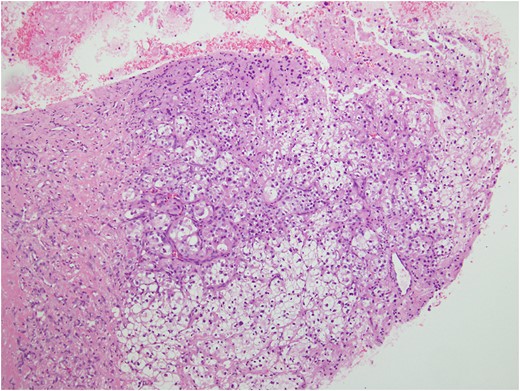

Histologic sections of the mass show distinct variably sized and shaped collections of uniform polygonal tumor cells, separated by fibrovascular septa and delicate capillary-sized vascular channels lined by flattened endothelium at low magnification (Fig. 5). Within the tumor nests, there is loss of cellular cohesion and necrosis of the centrally located cells in the nests results in the pseudo-alveolar pattern (Fig. 6). Vascular invasion is also present (Fig. 7). The individual tumor cells have distinct cell borders and abundant eosinophilic to clear, somewhat granular cytoplasm surrounding a central nucleus with variably sized nucleolus. Nuclear atypia is rarely seen. Mitotic figures are uncommon. The cells contain rhomboid or rod-shaped crystalline inclusions that are faintly apparent on routine histology and are better demonstrated with periodic acid-Schiff stain after diastase digestion (Fig. 8).

Tumor cells are arranged in organoid or nesting pattern. The nests are vary in size and shape and are separated by delicate thin fibrous septa containing vascular channels.

ASPS has a distinctive and characteristic, nested or organoid growth pattern. The nests tend to be uniform in size and shape, although some variations may be present. The nests are separated by delicate sinusoidal vascular channels lined by a flattened, single layer of endothelial cells. The cells may appear discohesive with focal necrosis in the center of the nests giving rise to the so-called, commonly seen, pseudo-alveolar pattern [6].